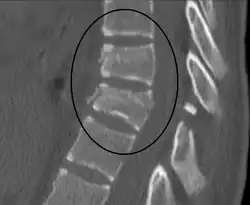

| A Chance fracture of T10 and fracture of T9 due to a seatbelt during an MVC. | |

| Diagnostic method | Medical imaging (X-ray, CT scan)[1] |

The cause is classically a head-on motor vehicle collision in which the affected person is wearing only a lap belt.[2] Being hit in the abdomen with an object like a tree or a fall may also result in this fracture pattern.[12][10] It often involves disruption of all three columns of the vertebral body (anterior, middle, and posterior).[7][6] The most common area affected is the lower thoracic and upper lumbar spine.[6] A CT scan is recommended as part of the diagnostic work-up to detect any potential abdominal injuries.[5] The fracture is often unstable.[1]

A CT scan of the chest, abdomen, and pelvis is recommended as part of the diagnostic work-up to detect any potential abdominal injuries.[5][10] MRI may also be useful.[10] The fracture is often unstable.[1]